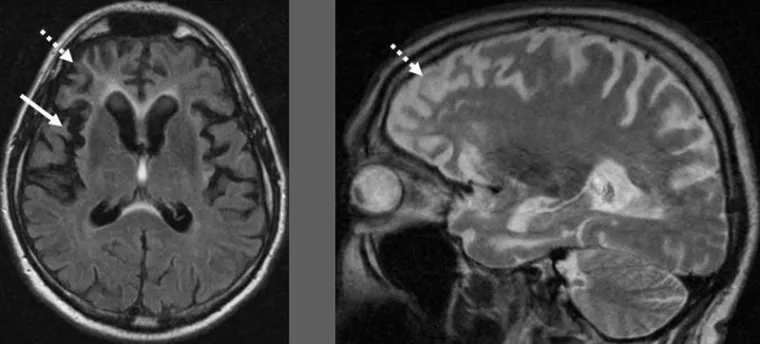

Die beteiligten Gene haben Einfluss auf Signalwege im Inneren der Nervenzellen. Je nach Gen handelt es sich um einen anderen Weg mit anderen Auswirkungen. „Was die Genfehler eint, ist, dass sie alle letztendlich dazu führen, dass Nervenzellen im Stirn- und Schläfenbereich des Gehirns absterben“, erklärt Mitautor Professor Dr. Peter Heutink. „Das Gute jedoch ist: Wir glauben, dass wir künftig in einige der Signalwege eingreifen und dadurch die Krankheit verlangsamen können.“ Ausschlaggebend ist, dass der Arzt weiß, welches Gen und Signalweg beim jeweiligen Patient betroffen ist. „Für die Diagnostik und zukünftig die individualisierte Therapie der Frontotemporalen Demenz sollte daher die Untersuchung des gesamten Erbguts an erster Stelle stehen.“